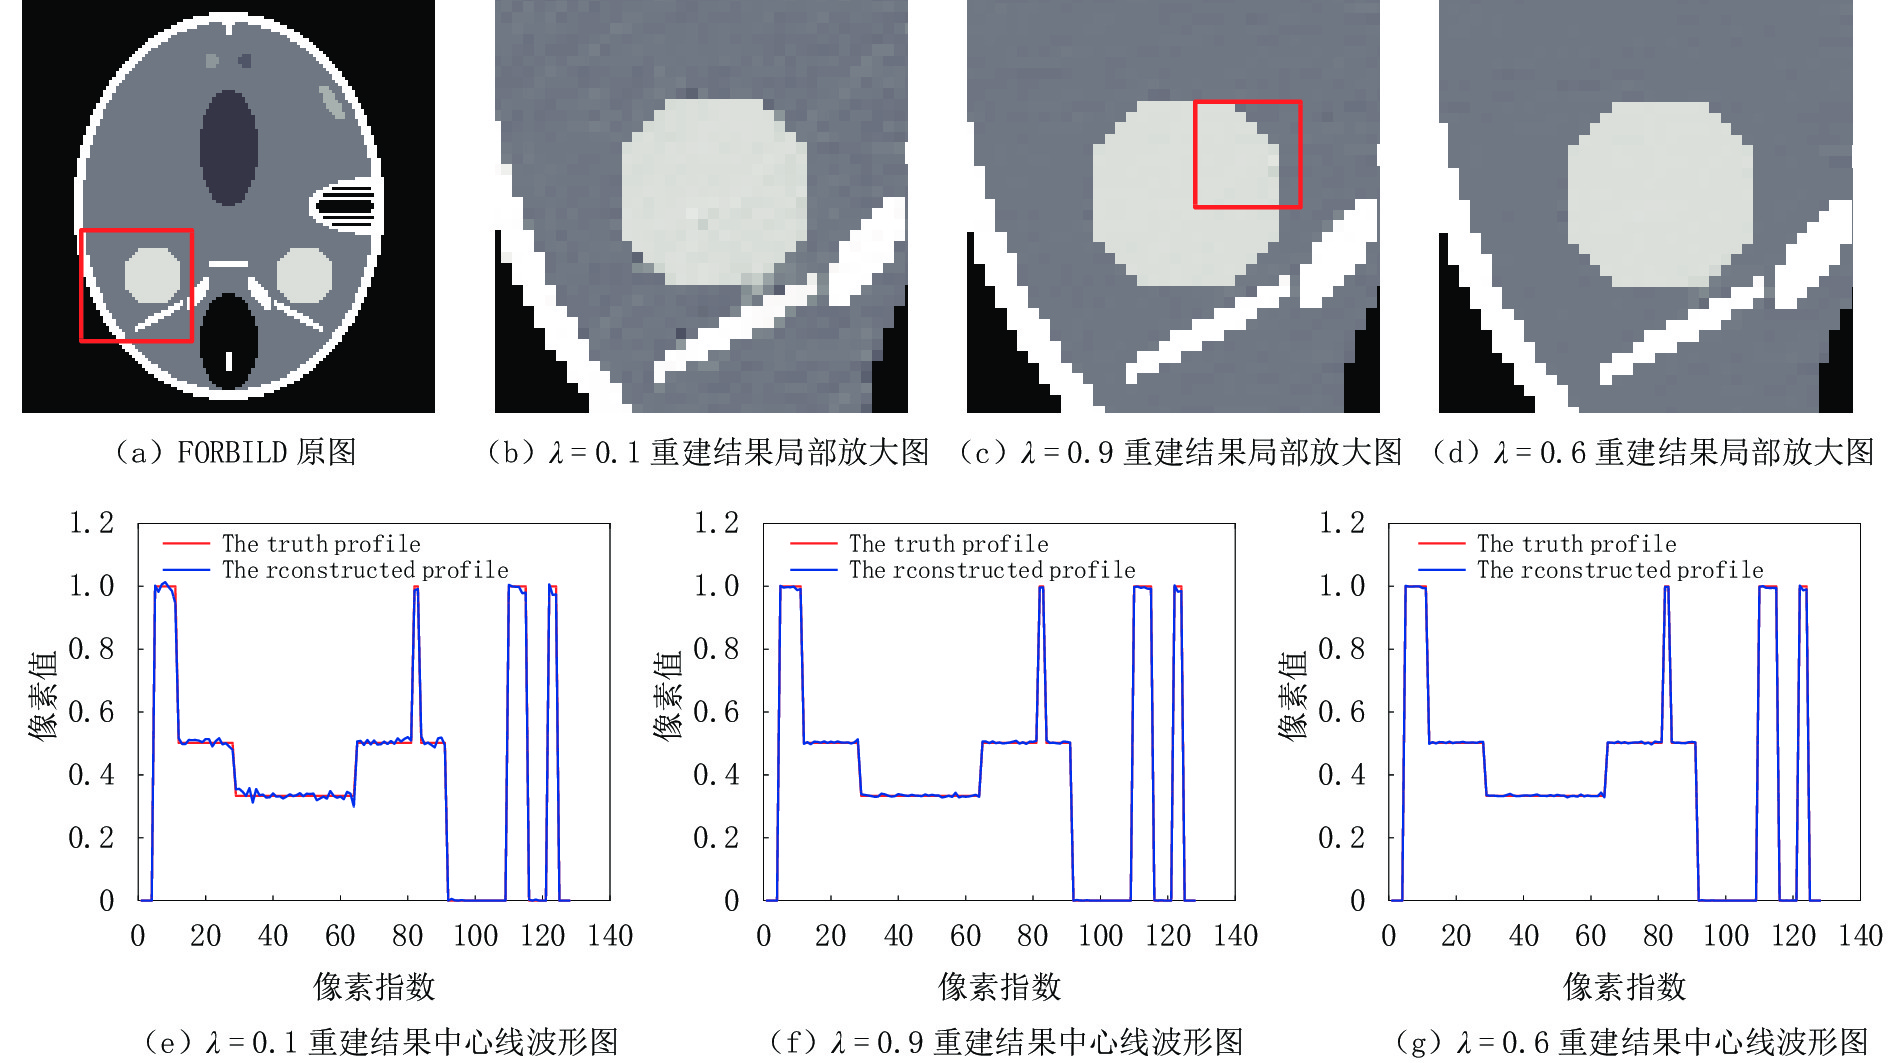

为了探索参数λ不同数值的选取对重建结果的影响,本节实验从0.01到1之间选取了20个不同的数值,然后选择0.1、0.6和0.9三个代表性结果做出讨论。

实验结果如图12所示,图12(a)是原图,图12(b)~图12(d)分别是λ选取不同数值重建结果的局部放大图。图12(e)~图12(g)分别是不同数值重建结果各自所对应的中心线波形图。如图12(c)所示,当λ取0.9时,与图b相比较大的λ可以增加RTV正则项的权重,在有效保护图像结构的同时还可以明显的减少伪影。然而,与图12(d)相比,过大的λ又会使重建图像丢失一些细节。从图12(g)图中可见,当λ=0.6时,其重建图像的中心线波形图与原图的几乎完全重合。所以如果选择合适的λ,在有效抑制伪影的同时还可以很好的保护图像结构。